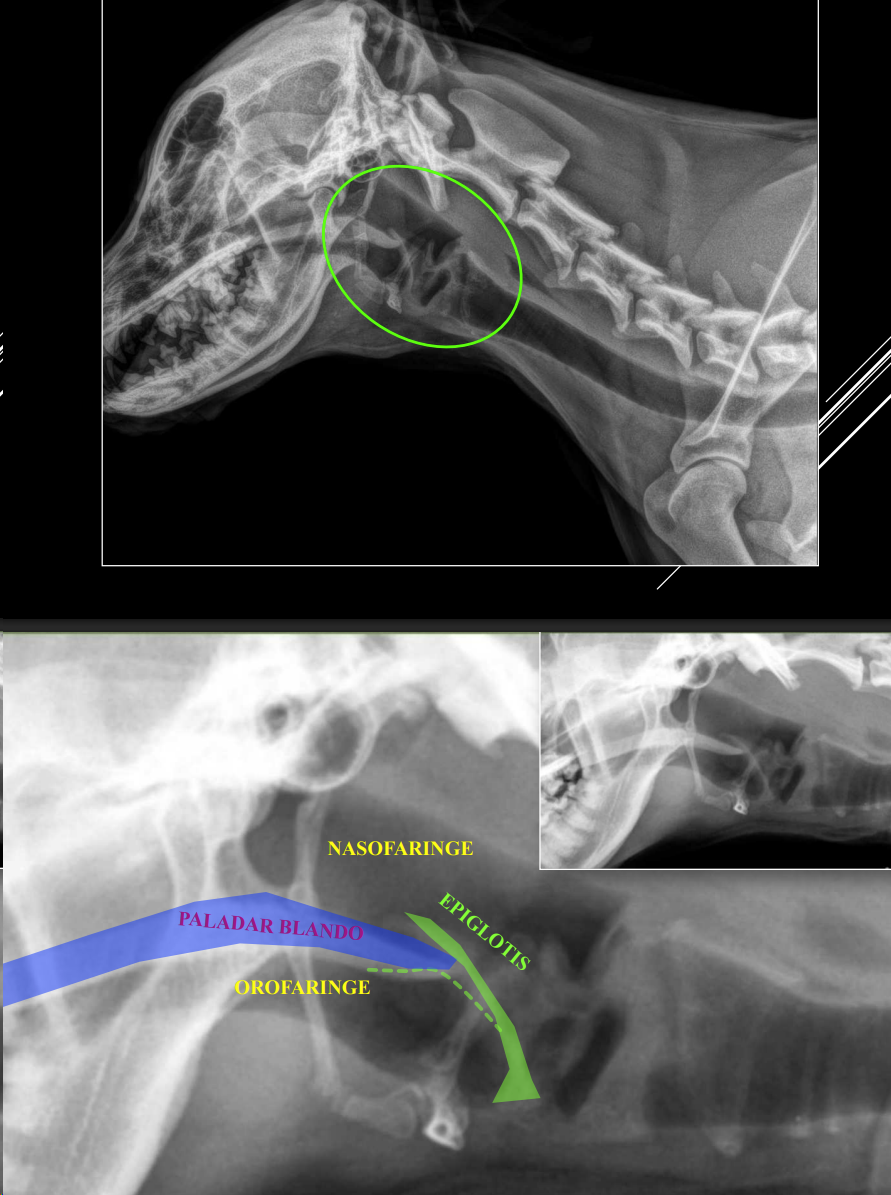

LARINGE

- Proyección LL, cabeza normal.

- Visible ventral a C1–C2.

- Estructuras: epiglotis, paladar blando, cartílagos hioideos.

- Patologías: engrosamiento, elongación, neoplasias, cuerpos extraños.

- Relevancia en razas braquicéfalas.